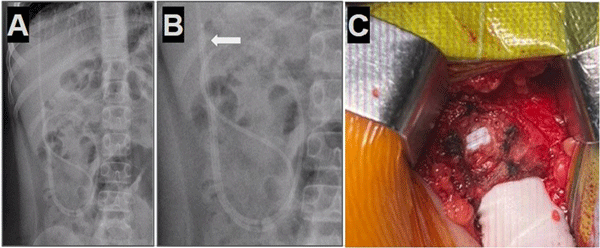

Se realizó la revisión quirúrgica del sistema de derivación ventriculoperitoneal en su porción distal o abdominal en todos los casos, durante esta, se pudo constatar la correcta salida de LCR gota a gota en todos los pacientes intervenidos, motivo por el cual se decidió la reintroducción del catéter distal en la cavidad peritoneal con cierre de la celiotomía y fijación del catéter utilizando la técnica de sutura en “bolsa de tabaco” para evitar la recidiva (Figura 6).

Figura 6. Se observa demostración de cierre de celiotomía con técnica de sutura “en bolsa de tabaco” realizada en modelo de simulación quirúrgica.

La evolución fue favorable, con resolución del cuadro sintomático en todos los casos, los pacientes recibieron el alta hospitalaria a las 48 horas postoperatorias y se realizó el seguimiento ambulatorio de forma trimestral durante los primeros 12 meses y posteriormente control anual. Ningún paciente presentó recidiva de esta complicación luego de la intervención realizada.

En nuestra experiencia, con los cinco casos presentados, luego de evaluar en forma detallada el cuadro clínico y las imágenes de cada paciente, planteamos una estrategia quirúrgica diferente a la revisión convencional del sistema de derivación ventriculoperitoneal: en lugar de reincidir y realizar la apertura de la cicatriz cefálica, optamos directamente por la apertura de la incisión abdominal previa y realizamos la exploración y revisión del catéter distal, en todos los casos evidenciamos la salida de líquido cefalorraquídeo a través de este, motivo por el cual asumimos los cuadros como disfunciones parciales del sistema por localización ectópica de la punta del catéter distal. Se reposicionó el catéter dentro de la cavidad peritoneal en todos los pacientes con cierre de la celiotomía y fijación del catéter mediante la técnica de sutura tipo “bolsa de tabaco”; con esta maniobra se logró el correcto funcionamiento del sistema con buena evolución postoperatoria y sin intercurrencias, preservando de esta forma la integridad de la cicatriz cefálica. En el último caso, además, nos apoyamos en la ecografía intraoperatoria para mejor localización del catéter, una herramienta de amplia disponibilidad que recomendamos utilizar, ya que de forma rápida y segura nos permite tener una imagen en tiempo real y a un bajo costo. Este enfoque quirúrgico reduce las posibilidades de complicaciones tales como infecciones asociadas a prótesis al reducir el tiempo quirúrgico y la exposición de la porción cefálica del sistema, acorta los tiempos de anestesia minimizando reacciones adversas y efectos secundarios a la misma, además favorece una recuperación postoperatoria más rápida, reduciendo la estancia hospitalaria optimizando recursos y disminuyendo los costos para el sistema de salud.